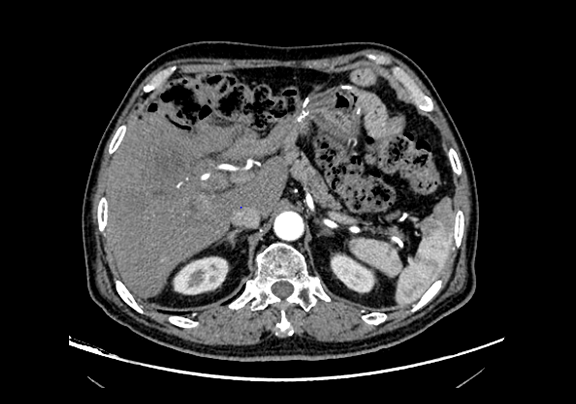

下腹部增强CT示:肝右前叶胆管细胞癌并胆管扩张可能性大。

将0.625mm双源薄层CT资料的静脉期和动脉期Dicom格式文件导入海信CAS系统。

通过调节窗宽窗位调整CT序号,对肿瘤,肝实质,胆囊,下腔静脉,肿瘤,肝动脉、门静脉及肝静脉等进行三维重建;系统自动计算肿瘤体积和肝脏体积。(图2—截图1---后链接截图2)

模拟手术操作,自动计算切除肿瘤体积。肝脏体积为1324ml,肿瘤体积为286.1ml,肿瘤体积为肝脏体积的21.6%,通过比对70-80岁正常肝脏体积为1118.08±190.14ml,通过术前模拟手术,精准判断切除后剩余肝脏体积能耐受,避免肝衰竭发生。术前手术方案的规划。

术前CT检查:

平衡期